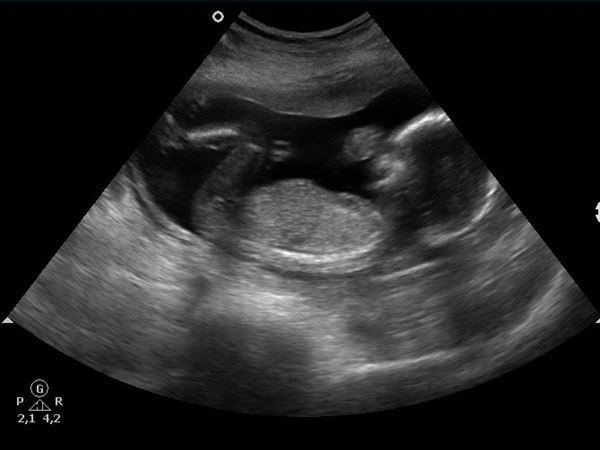

Jeg havde jo gået og undret mig over at jeg i 1. graviditet allerede mærkede liv i uge 16 og ikke rigtigt endnu denne gang. Så havde fået gjort mig selv ret nervøs da jeg havde en klar forventning om at jeg ville mærke liv før eller senest samme tidspunkt som sidst. Så var kommet ud i et skrækscenarie om at det måske var fordi der var noget galt, og at det var derfor babyen havde set lille ud til NF scanningen (blev rykket 8 dage tilbage). Da der er 1 mnd til MD scanning besluttede jeg mig for at bruge 500 kr på en privat scanning så jeg kunne blive beroligt med at der var liv i babyen og at alt så fint ud.

Vi var til scanningen i dag og der var godt liv i maven, så det var rigtig rart. Er meget lettet og tror på at jeg kan få slappet mere af frem til MD scanningen nu.

Alexander havde sagt at han mente det blev en baby med tissemand og det fik han ret i. Han skal have en lillebror

Vedhæftede fotos (klik for at se i fuld størrelse)